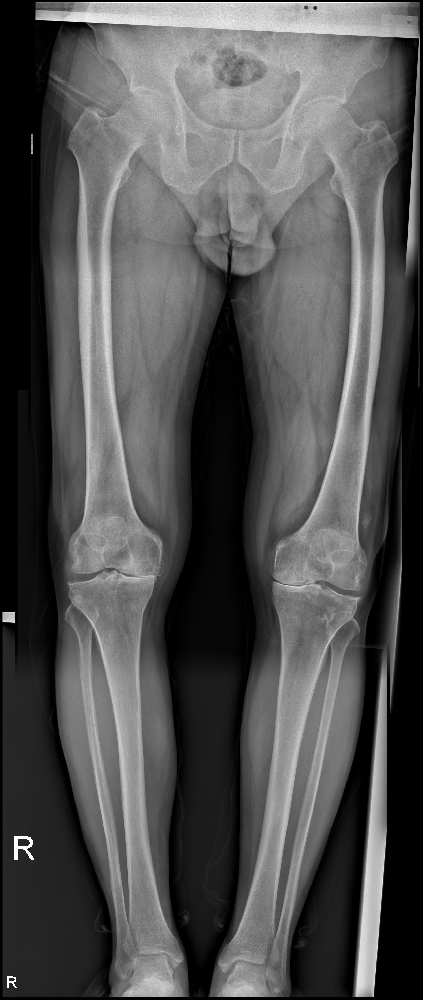

馬廣良的堅(jiān)持和決心打動(dòng)了醫(yī)院的醫(yī)生和護(hù)士,他們給予她最貼心的照顧和專業(yè)的建議。經(jīng)過一系列完善的檢查,醫(yī)生發(fā)現(xiàn)她的左膝關(guān)節(jié)內(nèi)側(cè)已經(jīng)受到嚴(yán)重的損傷,需要進(jìn)行手術(shù)治療,以恢復(fù)她的正常生活。

手術(shù)是一次考驗(yàn)醫(yī)生技術(shù)和馬廣良意志力的時(shí)刻。馬廣良選擇了手術(shù),并接受了左膝關(guān)節(jié)內(nèi)側(cè)活動(dòng)平臺(tái)單髁置換術(shù)。手術(shù)雖然對她來說充滿了一份未知,但她相信這將是獲得新生的關(guān)鍵一步。